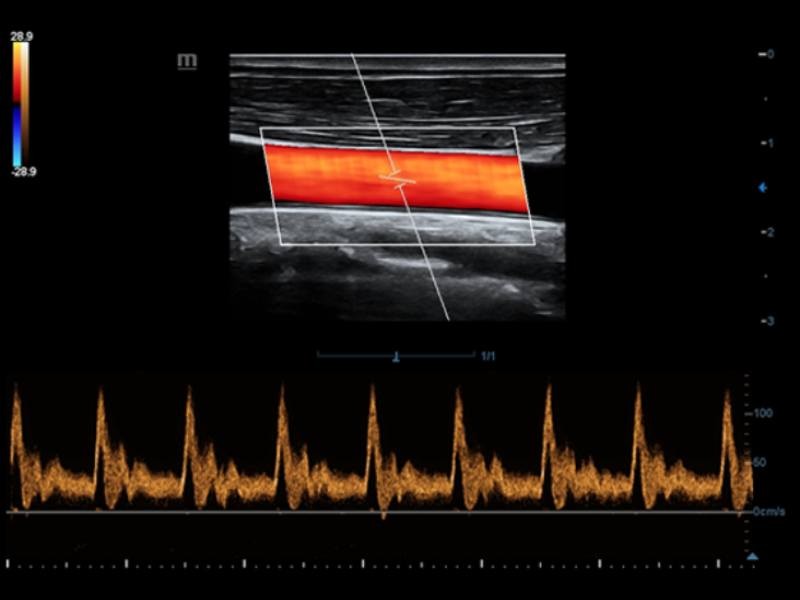

Trilha Inteligente

O Smart Track proporciona uma otimização rápida e inteligente das imagens vasculares com apenas um toque. Ele pode otimizar o espectro de cor, energia e PW por meio de rastreamento automático e reduz as etapas demoradas. Portanto, o fluxo de trabalho do exame vascular é simplificado por meio de uma visão ideal.